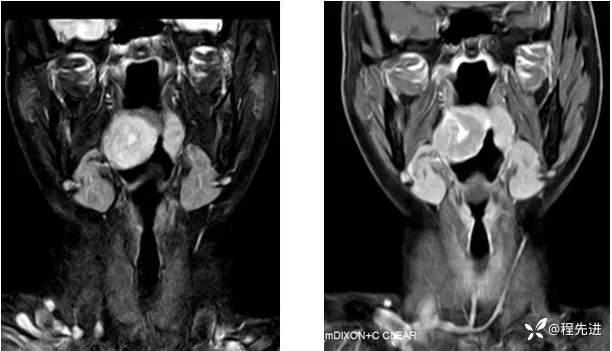

T1及T1增强:

T2压脂、T1压脂增强: